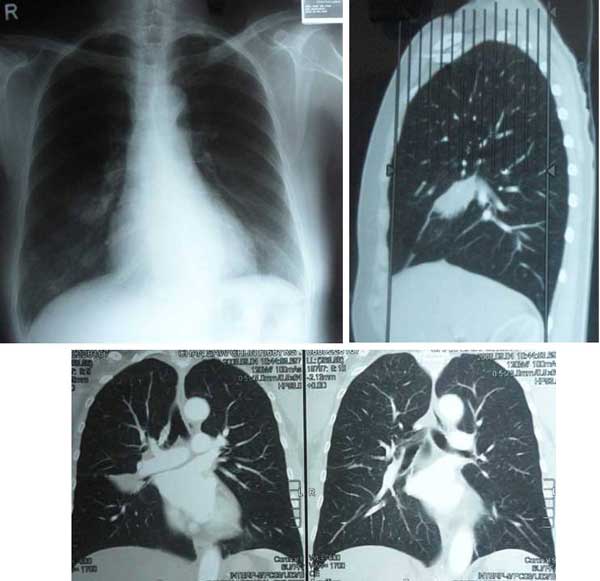

SC (H222) was 68 years old when her problem started. She is a non-smoker. She started to have coughs for the past six months. There were no other symptoms apart from pains at the right shoulder blade. A CT scan on 4 September 2008 showed a 3.0 x 4.75 x 3.0 cm opacity in right middle lobe of her lungs, suggestive of a neoplastic mass. Bronchial brushings showed moderately large neoplastic cells. Her blood test was normal, apart from a mildly elevated CEA (8.0).

CT scan on 4 September 2008.

SC underwent a CT scan of her brain and abdomen and these were normal. Her bone scan was negative for metastasis.